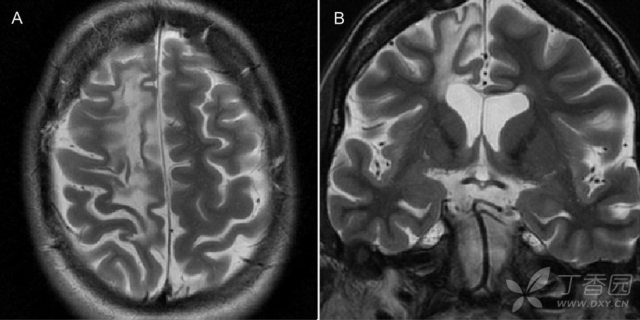

图 8:活检证实的 37 岁难治性部分性运动性癫痫伴 Rasmussen 脑炎女性患者;A~B:T2WI 可见右侧额叶萎缩和胶质增生

其特征性 MRI 表现为单侧脑沟、脑回及侧脑室扩大,皮层及皮层下脑白质在 T2/FLAIR 上高信号,基底节尾状核头部轻、重度萎缩。通常,急性期 MRI 显示单侧半球萎缩,最先由颞叶岛盖开始,伴有颞角萎缩,侧裂扩大。皮质萎缩常在单侧额岛叶进行性发展,通常累及额叶、岛叶、额岛叶、额颞岛叶、顶颞岛叶和额顶-枕岛叶。